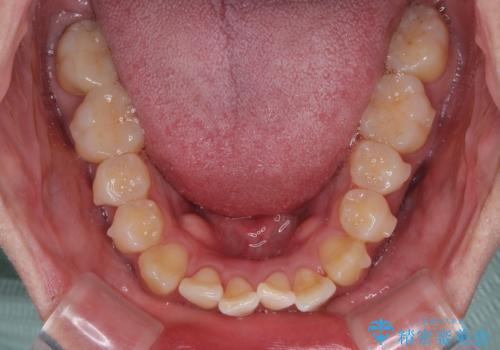

- 前歯の反対咬合などを気にして来院された患者様です。

ワイヤー矯正、マウスピース矯正どちらでも対応可能であったので、ご本人の希望によりインビザラインにて矯正治療を行うこととしました。

毎日の装着時間をしっかりと守ってくださり、1年強の短期間で、あっという間に治療を終えることができました。